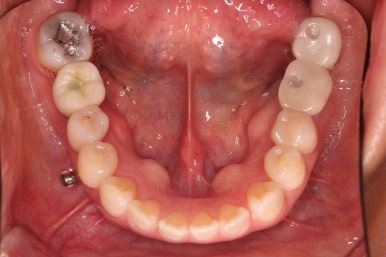

초진 시 입안의 모습입니다.

아랫니 큰 어금니 하나가 없어서 임플란트를 원하셨던 환자분이셨어요.

치아가 빠진지 오래되어 앞뒤 치아가 모두 반자리로 쓰러진 상태였어요.

그래서 큰 어금니 사이즈의 임플란트가 식립되지 못하는 상황이었어요.